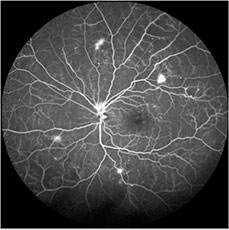

While a photograph of the retina provides a snapshot at one instant in time, an angiogram is a series of pictures that reveals the pattern of blood flow in the retina over a small period of time. Angiograms can be helpful for many conditions. For example, with an angiogram, your doctor will be better able to determine if the blood flow in the back of the eye is adequate, if there is inflammation within the blood vessels of the retina, if there is leakage of fluid and if so where that leakage comes from. These are only a few of the ways in which this important test can be helpful.

Sodium fluorescein is a dye used in fluorescein angiography (FA). The fluorescein dye is injected into the bloodstream (usually through a vein on the arm or hand). The dye will circulate in the blood vessels of the retina, and will give off a fluorescent color when light passed through special filters is focused on the retina. Dynamic pictures of the blood flow inside the eye are then taken.

FA can take 5 to 10 minutes to perform and involves a small needle-stick. After dilation, you will be seated comfortably, and the doctor will inject a small amount of fluorescein dye into a vein on your arm or hand. At the same time, you will be instructed to place your chin in a chin-rest on the machine. You will then be instructed to look at a target while our skilled photographer takes digital photographs using the necessary filters. Your doctor will review the results with you in the examination room.